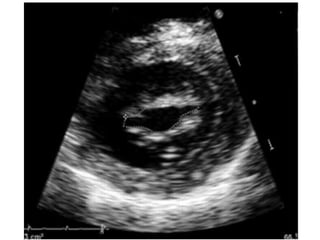

Measuring valve area

1. MVA Planimetry (Level 1 Recommendation).

planimetry is considered as the reference

measurement of MVA

• Careful scanning from the apex to the base of

the LV PSAX view at the level of mitral valveis

required to ensure that the CSA is measured

at the leaflet tips

• Gain setting should be just sufficient to

visualize the whole contour of the mitral

orifice. Excessive gain setting may cause

underestimation of valve area, in particular

when leaflet tips are dense or calcified.

• Image magnification, using the zoom mode, is

useful to better delineate the contour of the

mitral orifice.

Measuring valve area 1.MVA Planimetry (Level 1 Recommendation). planimetry is considered as the reference measurement of MVA • Careful scanning from the apex to the base of the LV PSAX view at the level of mitral valveis required to ensure that the CSA is measured at the leaflet tips

• Gain settingshould be just sufficient to visualize the whole contour of the mitral orifice. Excessive gain setting may cause underestimation of valve area, in particular when leaflet tips are dense or calcified. • Image magnification, using the zoom mode, is useful to better delineate the contour of the mitral orifice.